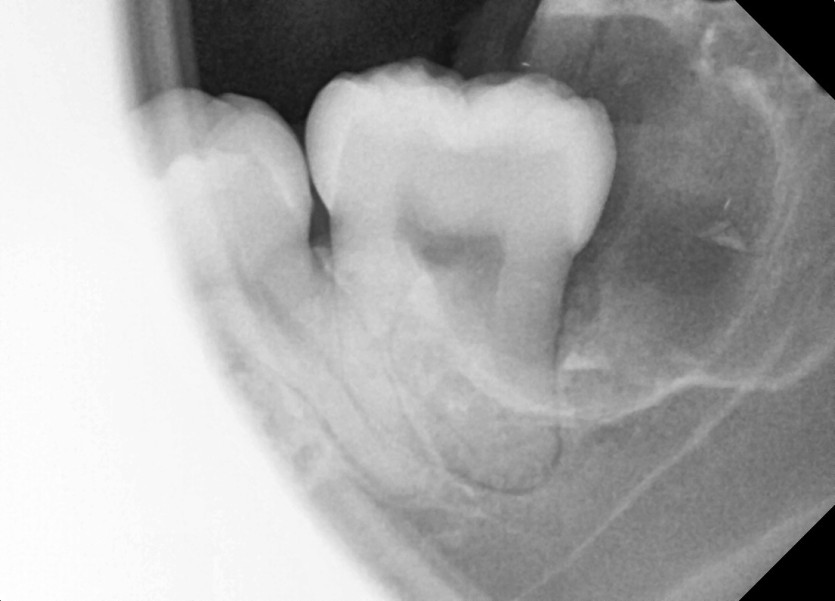

#28,38 사랑니 발치

구강외과 전문의가 당일 발치했습니다.